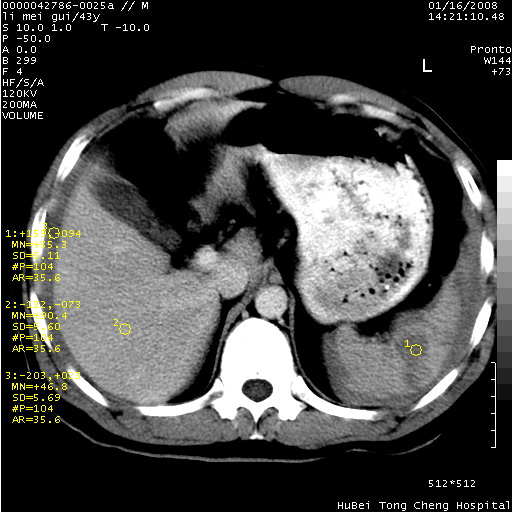

| 患者,男,43岁。突发腹痛2小时,面色苍白,难以平卧。自述近期无明确外伤史,为摩托车驾驶员。 腹部b超检查:脾脏中上极回声异常,肿瘤待排。 临床诊断:腹痛原因待查。 上中腹部ct轴位平扫+增强扫描(层厚10mm,螺距1.0,重建间隔10mm),图像如下: ![]() ![]() ![]() ![]() ![]() ![]() ![]() ![]() ![]() ![]() ![]() ![]() ![]() ![]() ![]() ![]() ![]() ![]() ![]() ![]() ![]() ![]() ![]() ![]() ![]() ![]() ![]() ![]() ![]() ![]() ![]() ![]() ![]() ![]() ![]() zrs发言:支持脾破裂 wwp发言:支持脾破裂并腹水。 xulianj发言:脾脏肿瘤破裂可能性大 zsl6918发言:不像肿瘤出血,考虑还是与外伤后引起的慢性出血有关 zzyy发言:平扫见肝周及脾周积液,脾内密度不均。脾内肿瘤较少见。还是外伤性脾破裂。 沈丘东方医院发言:脾门区一个不均匀强化病灶与其周液体相连多考虑脾占位破裂出血 yixianman001011发言:脾破裂并腹水是可以肯定的,具体原因多以肿瘤性破裂出血,脾脏淋巴瘤可能性大. 结果: 术后,经详细询问患者,其仔细回忆:一月前骑摩托时左侧腰部与别人有“轻微”触碰,因责任在自已,当时又无明显不适,未引起注意。 临床术后诊断:脾破裂并失血性休克(1.外伤性迟发性脾破裂。2.脾脏肿瘤破裂?) 术后标本病检:脾破裂并出血,未见明显肿瘤成份。 原贴地址:http://www.radinet.com.cn/forum_view.asp?forum_id=4&view_id=34070 |